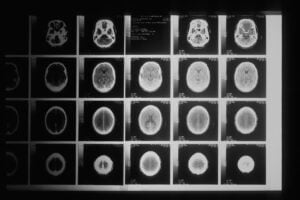

Addiction is the outcome of a process of changes in the brain’s reward system. The reward system in our brain evolved to help us survive by making us seek rewards or pleasure, avoid pain, and all with the least possible effort or expenditure of energy. We love novelty, especially if we can experience pleasure or avoid pain with less effort. Food, water, bonding and sex are the basic rewards we have evolved to seek in order to survive. The focus on them developed when these necessities were scarce, so we experience pleasure when we find them. These survival behaviours are all driven by the neurochemical dopamine, which also strengthens the neural pathways that help us learn and repeat the behaviours. When dopamine is low, we feel urges to prompt us to seek them out. While the desire to seek the reward comes from dopamine, the feeling of pleasure or euphoria from getting the reward comes from the neurochemical effect of natural opioids in the brain.

Four key brain changes happen in the process of addiction.

First we become ‘desensitised’ to ordinary pleasures. We feel numb around ordinary everyday pleasures that used to make us happy.

The addictive substance or behaviour works with the second main change, ‘sensitisation’. This means that instead of enjoying pleasure from many sources, we become over-focused on our object of desire or anything that reminds us of it. We believe we can only feel satisfaction and pleasure through it. We build tolerance i.e. we become used to the higher level of stimulation that relieves the discomfort of withdrawal from it.

The third change is ‘hypofrontality’ or the impairment and reduced functioning of the frontal lobes that help inhibit behaviour and allow us to feel compassion for others. The frontal lobes are the brakes that put a hold on behaviours we need to control. It is the part of the brain where we can put ourselves into the shoes of others to experience their point of view. It helps us cooperate and bond with others.

The fourth change is the creation of a dysregulated stress system. This leaves us hypersensitive to stress and easily distracted, leading to impulsive and compulsive behaviour. It is the opposite of resilience and mental strength.

Addiction results then from repeated and increasingly intense use of a substance (alcohol, nicotine, heroin, cocaine, skunk etc) or a behaviour (gambling, internet pornography, gaming, shopping, eating junk food) that causes changes to the brain’s structure and functioning. Everyone’s brain is different, some people need more stimulation than others to experience pleasure or become addicted. The constant focus on and repetition of a particular substance or behaviour signals the brain that this activity has become vital for survival, even when it is not. The brain reorders itself to make that substance or behaviour a top priority and devalues everything else in the user’s life. It narrows a person’s outlook and diminishes their quality of life. It can be seen as a form of ‘over learning’ when the brain gets stuck in a feedback loop of repeated behaviour. We respond automatically, without conscious effort, to something around us. This is why we need strong healthy frontal lobes to help us think consciously about our decisions and respond in a way that promotes our long term interests and not just short term urges.